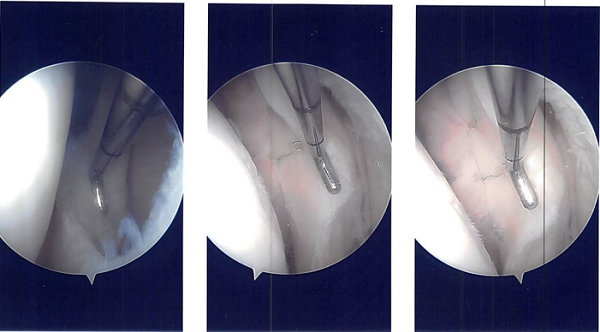

Arthroscopic surgery was performed. Lateral anterior portal was made for arthroscopic viewing. The scope was entered and the camera was entered. The camera showed a tear of the posterior horn and brought the posterior body of the lateral meniscus around the popliteal hiatus at its periphery.

The tear was repairable and I decided to repair it. There was a grade 2 to grade 3 chondral lesion over the patella as well as lateral condyle of the femur. Chondroplasty was performed. The meniscal rasp was used to prepare the capsular as well as the meniscal attachment.

A plane was made between the popliteus and the gastrocnemius with the vessels behind. Sims speculum was used to retract the vessels posteriorly. Another scope was reintroduced on the lateral border and all-inside repair was done using FasT-Fix with a Nephew curved all-inside implant and sutures.

Three of them were put in the body posterior and medial to the popliteus muscle and one was put lateral to the popliteus muscle. The reduction and repair were found to be adequate. The tourniquet was released and found to have a good blood clot inside.